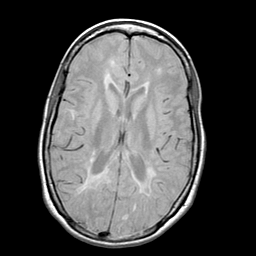

Multiple Sclerosis, MR Study mr-pd -- Slice #12

[Home][Help][Clinical] Slice 12